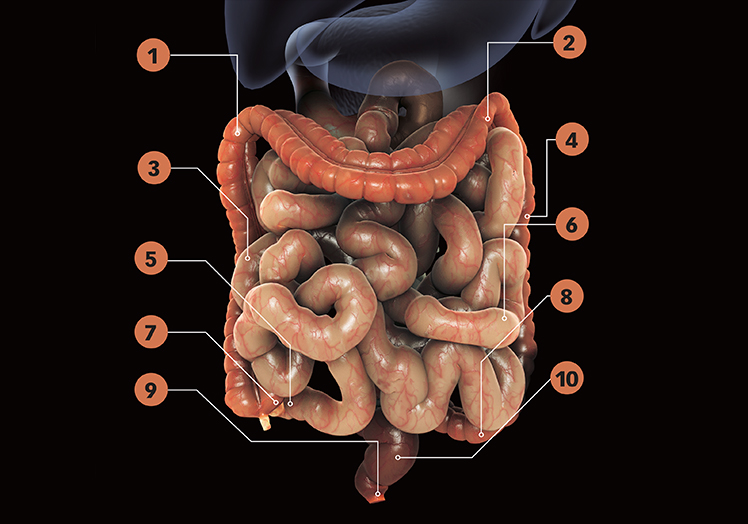

1. Colon ascendente: el agua y las sales minerales son absorbidas a lo largo del intestino grueso, en un proceso que deseca los restos alimentarios.

2 Colon transverso: los restos no digeridos comienzan a ser transformados en heces.

3 Duodeno: parte inicial del intestino delgado, a las que se dirigen las secreciones del páncreas y del hígado.

4 Colon descendente: las heces se consolidan y se acumulan antes... Leer más

El intestino delgado mide entre 6 y 7 metros y el grueso promedia 1,5 metros. Sus respectivas constituciones y funcionalidades son complementarias. Ambos tienen una membrana protectora externa serosa y también una submucosa, que es una capa suelta con vasos y nervios.

Sin embargo, la mucosa del intestino delgado absorbe nutrientes a través de proyecciones o vellosidades, mientras que la mucosa del intestino grueso secreta... Leer más

La pared interna del intestino delgado está revestida de millones de proyecciones llamadas ‘vellosidades’. Cada una está dotada de un vaso linfático y una red de vasos sanguíneos que la nutren. Cada vellosidad está cubierta por una capa celular que absorbe nutrientes. Junto con estas células epiteliales existen unas microvellosidades que optimizan la absorción de nutrientes.